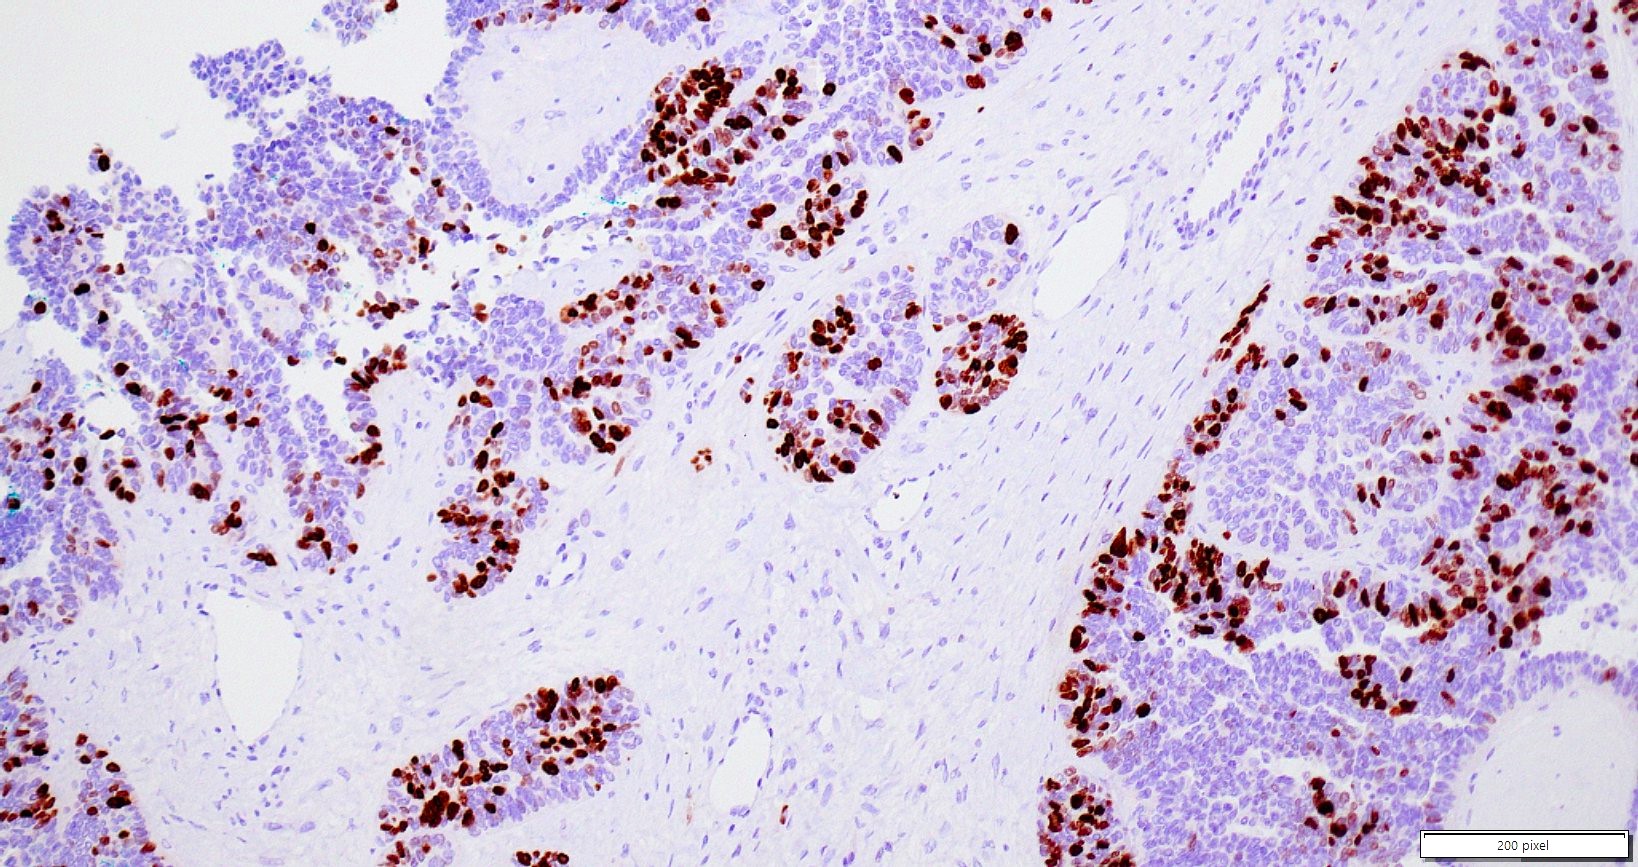

Microscopic (histologic) images

Contributed by Daniel Graham, M.D., Adele Wong, M.B., B.Ch., B.A.O. and Lucy Ma, M.D.

Positive stains

- PAX8: usually diffusely positive

- GATA3 and TTF1: focal or diffuse with inverse staining pattern described in several studies in the most recent WHO classification; cells positive for GATA3 are negative for TTF1 and vice versa (Am J Surg Pathol 2018;42:1596)

- CD10: focal and apical / luminal

- p53 wild type

- MMR proficient